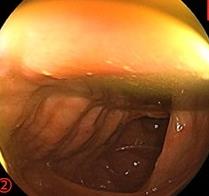

摘要:目的 探讨利那洛肽联合西甲硅油与复方聚乙二醇电解质散(PEG)对便秘患者肠道清洁效果的有效性和安全性。方法 采用前瞻性随机对照试验,通过单盲法,纳入2023年4月-2024年8月于该院消化内镜中心行结肠镜检查的便秘患者383例,随机分为常规组(128例)、实验A组(128例)和实验B组(127例)。常规组采用3 L PEG(Ⅰ)溶液,实验A组采用290 μg利那洛肽 + 2 L PEG溶液,实验B组采用290 μg利那洛肽 + 30 mL西甲硅油+2 L PEG溶液。比较3组患者的肠道准备效果[Boston肠道准备量表(BBPS)评分和去泡效果]、病变检出率、首次排便间隔时间、排便次数、盲肠插管成功率、进镜时间、退镜时间、不良反应发生率和重复检查意愿等。结果 3组患者BBPS评分比较,差异无统计学意义(P > 0.05);实验B组的去泡效果评分明显低于常规组和实验A组,差异均有统计学意义(P < 0.05);实验B组的病变总检出率和息肉检出率明显高于常规组和实验A组,差异均有统计学意义(P < 0.05);常规组的首次排便间隔时间明显长于实验A组和实验B组,差异均有统计学意义(P < 0.05);3组患者排便次数比较,差异无统计学意义(P > 0.05);3组患者盲肠插管成功率均为100.0%,进镜时间相当,差异均无统计学意义(P > 0.05);实验B组的退镜时间明显短于常规组和实验A组,差异均有统计学意义(P < 0.05);常规组腹胀腹痛发生率和不良反应总发生率明显高于实验A组和实验B组,差异均有统计学意义(P < 0.05);常规组重复检查意愿率明显低于实验A组和实验B组,差异均有统计学意义(P < 0.05)。结论 290 μg利那洛肽联合30 mL西甲硅油与2 L PEG溶液方案在便秘患者肠道准备上具有优势,较3 L PEG溶液和290 μg利那洛肽+2 L PEG溶液方案,可获得更好的肠道清洁效果,且安全性和患者重复检查意愿率高,可作为便秘患者肠道准备的推荐方案。